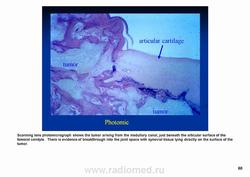

Рентгенологически выявляют в очаге деструкции участки обызвествления в виде крапчатости; кортикальный слой с признаками эрозии со стороны эндоста и истончения; размеры опухоли более 4 см; периостальная реакция слабо выражена или отсутствует; может наблюдаться деструкция кортикальной кости и наличие мягкотканного компонента; в длинных костях локализуется чаще в метафизах и диафизах; интенсивное внутрикостномозговое распространение.